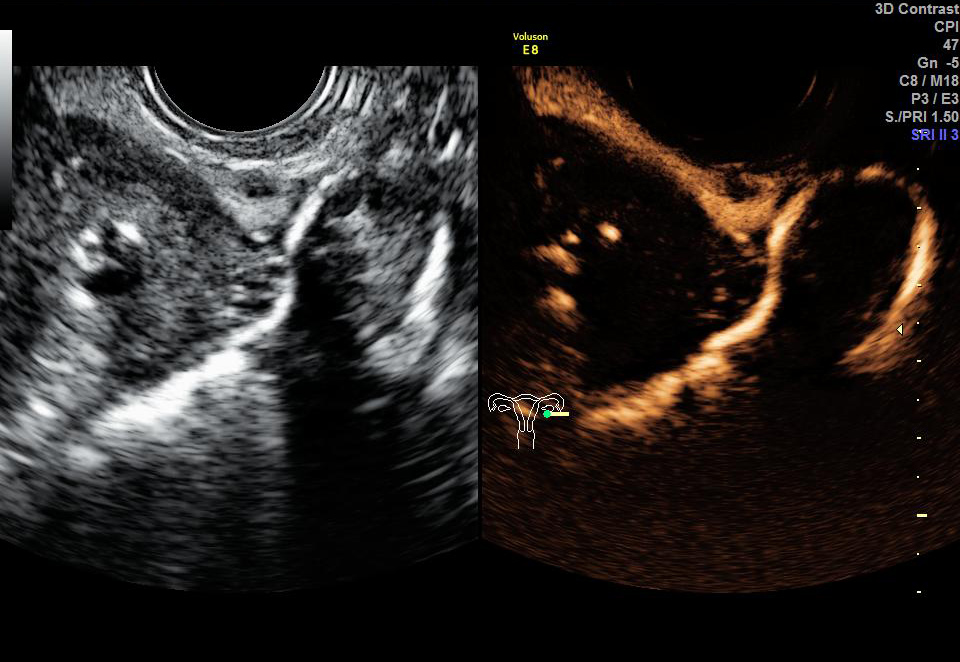

二维超声:观察子宫及双侧卵巢形态和结构变化,对子宫、输卵管、卵巢及盆腔的疾病做基础性排查。